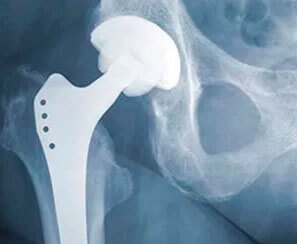

El reemplazo total de cadera es la cirugía de cadera más común. Utiliza componentes artificiales para reemplazar toda la estructura de la cadera. Durante el procedimiento, los cirujanos insertan un vástago en el fémur o el hueso del muslo del paciente para darle estabilidad. Reemplazan la cabeza del fémur con una bola y reemplazan la cavidad natural de la articulación de la cadera con una copa artificial.